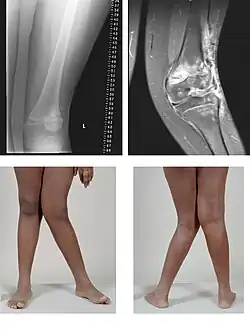

Genua valga

Genua valga of X-benen is een dubbelzijdige naar binnen gerichte buiging van beide benen. De buiging betreft een stand van het onderbeen waarbij dit in de knie ten opzichte van het bovenbeen naar buiten gebogen staat. De rechte lijn, die normaal door de heup, knie en enkelgewricht gaat, valt bij deze aandoening buiten en naast de knie, en ook de binnenenkels raken elkaar niet meer omdat de voeten niet naast elkaar geplaatst kunnen worden. Hierdoor lijkt het alsof beide benen een X vormen.

Er zijn twee soorten X-benen: de slappe X-benen die grotendeels te corrigeren zijn, en de benige verkrommingen. Meestal is er een combinatie van beide. Bij het gefixeerde X-been (benige verkromming) zit de verkromming meestal in het scheenbeen, maar soms ook in het dijbeen en het scheenbeen tezamen. Behalve door stofwisselingsstoornissen en congenitale afwijkingen kunnen X-benen ook veroorzaakt worden door het gebruik van de benen in een buitenwaarts gedraaide stand bij het kruipen. Wanneer de spieren sterk zijn en het skelet zwak ontstaan waarschijnlijk O-benen, terwijl bij een goed skelet en slappe spieren X-benen kunnen ontstaan in deze vroege ontwikkelingsfase.